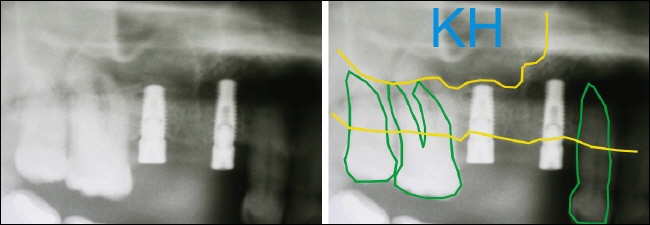

Ein typischer Fall im Oberkiefer Seitenzahngebiet – es ist nicht ausreichend Knochenhöhe vorhanden. Auf der rechten Seite sieht man die relevanten Strukturen des Röntgenbildes durch schematische Linien dargestellt. Die grünen Linien zeigen die Zahnumrisse, dazwischen ist die zu versorgende Lücke.

Die gelbe untere Linie entspricht dem Kieferkamm, der bis zur oberen gelben Linie verläuft. Über dieser oberen gelben Linie beginnt die Kieferhöhle (KH). Der Abstand zwischen den beiden gelben Linien zeigt, wie viel vertikaler Knochen (Knochenhöhe) vorhanden ist. Der rote Pfeil zeigt den unzureichenden Knochenabschnitt.